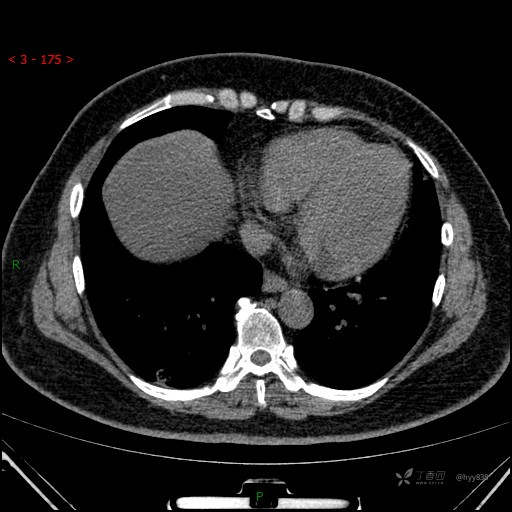

胸部CT平扫